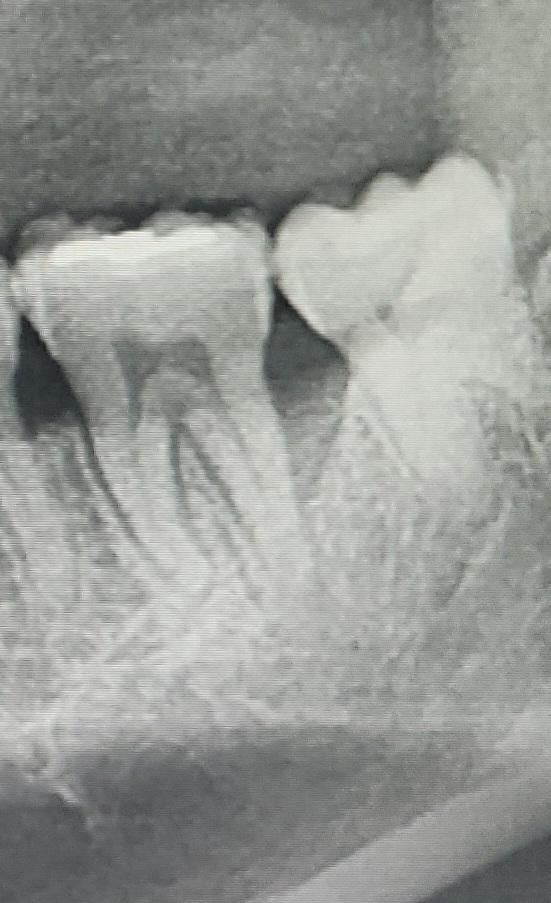

명절 중 사랑니와 맞닿은 어금니 부위 잇몸에 물집이 크게 잡혀 진료를 받아보니, 염증이 가라앉은 후 사랑니 발치하고 이 후에 맞닿은 어금니의 치료를 진행하여야 한다고 하셨습니다. 제가 오랫동안 사랑니를 방치한 상태로 유지하여 사랑니와 어금니 사이의 치조골이 많이 손상된 상태라고 하셨는데 이 후 어떤 치료를 받게 될까요? 발치까지 이어질 가능성이 있나요? ㅠㅠ

사진상으로 보면 뒤에서 두번째 치아 잇몸이 많이 안좋습니다. 최대한 사용하실때까지 사용하다가 발치를 하셔야될수도 있습니다.

어금니 원심측 잇몸뼈가 염증으로 녹아있는 상태이고 잇몸치료는 받아봐야 합니다 현재로선 증상없으면 발치는 안해도 됩니다 치아 원인이 아닙니다